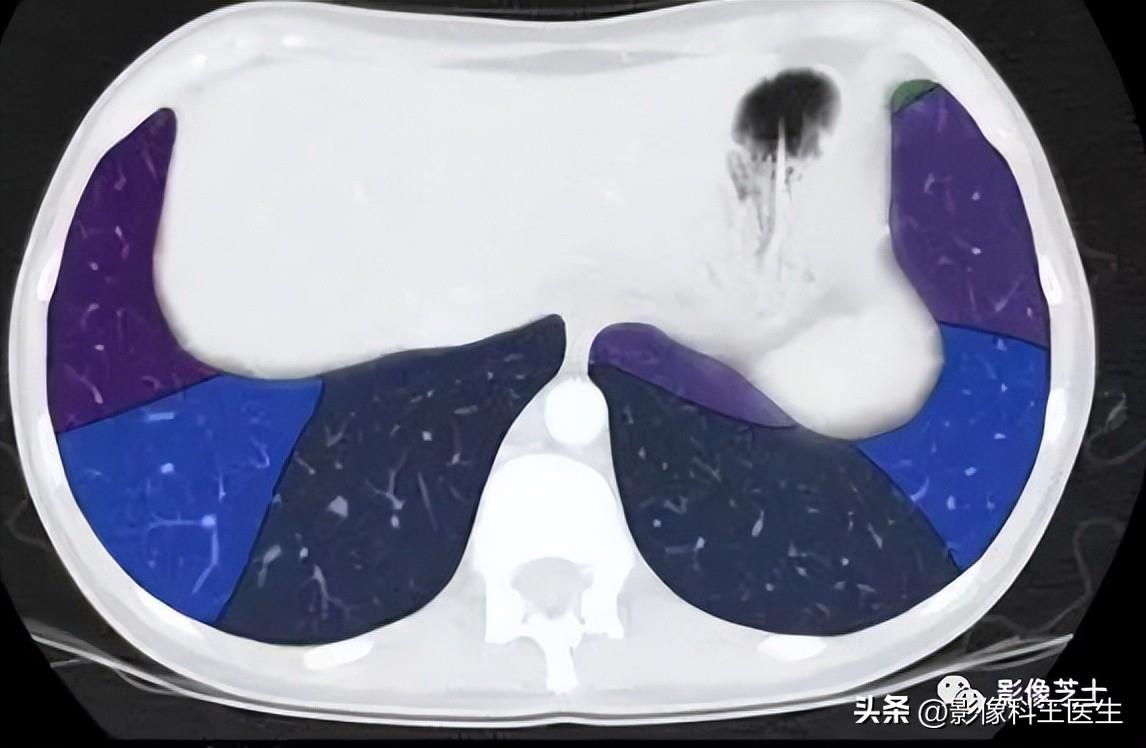

肺段、支气管分段CT解剖(详细标注)

肺部解剖分叶分段CT

分叶

先切到斜裂,后水平裂

左二右三

肺的分段